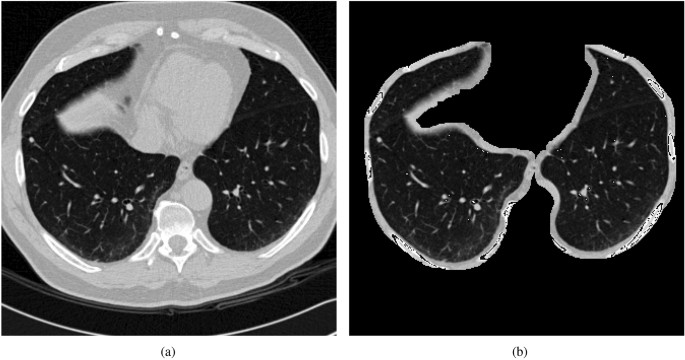

Each CT scan in the LUNA16 dataset includes a series of axial slices of the thorax, with the number of slices varying depending on the scanning equipment, slice thickness, and individual patients. Since the CT images in LUNA16 cannot be directly used for training neural networks, this study preprocesses the original dataset by converting it into PNG format. Subsequently, a deep learning-based method is employed to segment the lung parenchyma in the PNG images, excluding surrounding bones and muscles to minimize interference and enhance detection accuracy and recognition rates. Examples of the PNG images and their segmented counterparts are shown in Fig. 6.

Original images and segmented images.